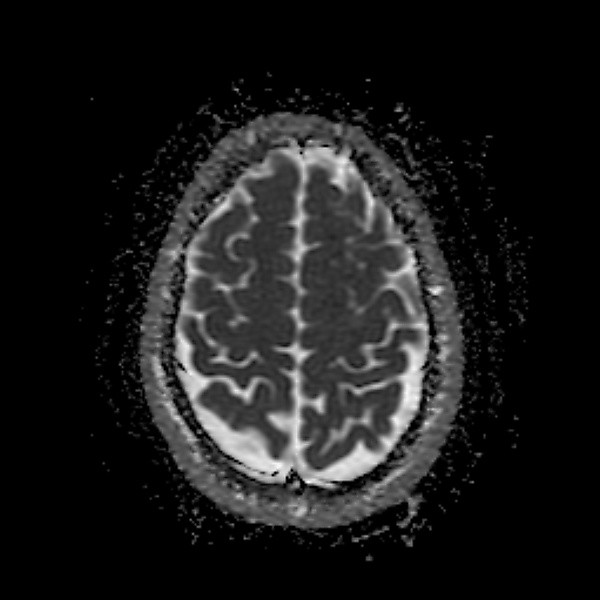

Диагностика

Проявления токсической энцефалопатии разнообразны и неспецифичны. Кроме того, один и тот же нейротоксин вызывает разные симптомы в зависимости от дозы и продолжительности воздействия (например, острое отравление сероуглеродом вызывает психоз, хроническое — атеросклероз). В большинстве случаев наблюдается зависимость «доза-реакция» — чем больше токсина поступает в организм, тем тяжелее симптомы; чем дольше токсин присутствует в организме, тем выше вероятность необратимых изменений. Среди работников вредных производств и жителей неблагоприятных экологических зон распространена бессимптомная токсическая энцефалопатия. Например, у людей, занятых в производстве красок или покрасочными работами, часто выявляют субклинические нейропсихологические нарушения[2].

Острая токсическая энцефалопатия проявляется спутанностью сознания, дефицитом внимания, судорогами и комой. В зависимости от токсина, дозы и индивидуальных особенностей организма неврологические симптомы могут исчезнуть после прекращения воздействия. Однако к необратимым нарушениям или смерти может привести даже однократное воздействие некоторых токсинов[3].

Хроническая токсическая энцефалопатия протекает скрыто в течение многих лет. Могут наблюдаться неустойчивость настроения, рассеянность внимания, утомляемость, вялость[1][3], головокружение, головная боль, тошнота, двигательные расстройства, когнитивные расстройства (дефицит внимания, памяти, обучения)[2].